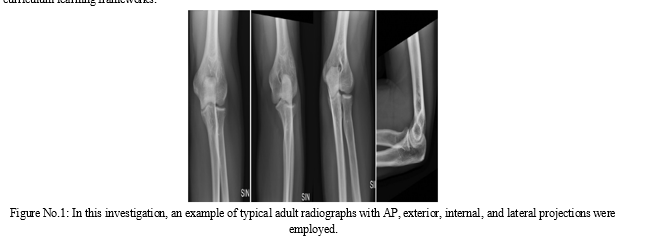

To detect an elbow fracture, patients typically need to take frontal and side views of diagnostic elbow radiographs. For the classification of elbow fracture subtypes, we propose a multiview deep learning technique in this work. Our strategy makes advantage of transfer learning by first training two individual models, one for the top view and another for the lateral position, and then moving the values to the relevant layers in the proposed multiview network design. Quantitative medical data has also been included into the training phase using a specific curriculum architecture that lets the model to initially learn from \"easier\" examples and then advance to \"harder\" examples to attain improved performance. Furthermore, our multiview network can work with both two simultaneous views as well as a single view as input. Using a database of 1,964 photographs for the classification of elbow fracture, we rigorously evaluate our methods. Results show that our technique may enhance the effectiveness of the tested methods and perform better than two comparable methods on broken bones investigation under various conditions. The sampling probability of each training sample is determined by a scoring criterion that was built using clinically reliable knowledge from human specialists, where the scoring indicates the diagnostic complexity of different elbow fracture subtypes. Additionally, we provide a technique that modifies the sampling probabilities at each epoch and is applicable to many sample-based curriculum learning frameworks. We design an experiment utilising elbow X-ray images from 1865 for a binary task of fracture/normal and compare our recommended strategy to a base classifier and an earlier method using different criteria. Our data show that the recommended technique performs the best in terms of categorization. The effectiveness of the earlier method is also enhanced by our recommended probability update mechanism.